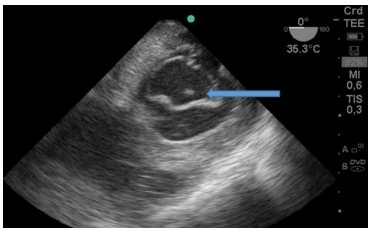

Durante el intraoperatorio, posterior al desclampeo, el paciente sufre descompensación hemodinámica aguda, con severa hipotensión y bradicardia extrema. En ese momento no se presentaban alteraciones metabólicas significativas en los estudios de laboratorio. Se comenzó con maniobras de reanimación cardiopulmonar avanzadas y se colocó ETE mediante el cual se pudo determinar la causa: trombosis masiva intracardiaca (TIC). En las siguientes imágenes se puede observar un trombo proveniente de vena cava inferior y además un cable de marcapaso situado en aurícula derecha. Figura 2.

Figura 2: Vista a 55 grados medio-esofágica: Imagen hiperdensa (flecha) de un gran trombo ingresando desde la vena cava inferior hacia la aurícula derecha